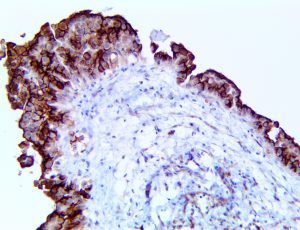

It is the ICU physician who is most likely to witness one of the deadliest manifestations of the abnormal immunological response, the cytokine storm syndrome (CSS). This response is also referred to by some as the cytokine release syndrome (CRS). CSS is characterized by continuous activation and expansion of macrophage and lymphocyte populations, which secrete large amounts of cytokines, causing the cytokine storm. This massive cytokine release is akin to hemophagocytic lymphohistiocytosis (HLH) disease, a syndrome characterized by initial unchecked and persistent activation of cytotoxic T lymphocytes and NK cells.

Clinical and laboratory manifestations of HLH include fever, enlarged liver and/or spleen, neurologic dysfunction, coagulopathy, liver dysfunction, cytopenias (i.e., low levels of erythrocytes, leukocytes, and/or platelets), hypertriglyceridemia, hyperferritinemia, hemophagocytosis, and eventually diminished NK cell activity as the immune system becomes progressively paralyzed. HLH can be familial (primary HLH) or secondary to another disease process (sHLH), such as rheumatic disease, in which it is referred to as macrophage activation syndrome (MAS, characterized by elevated ferritin).